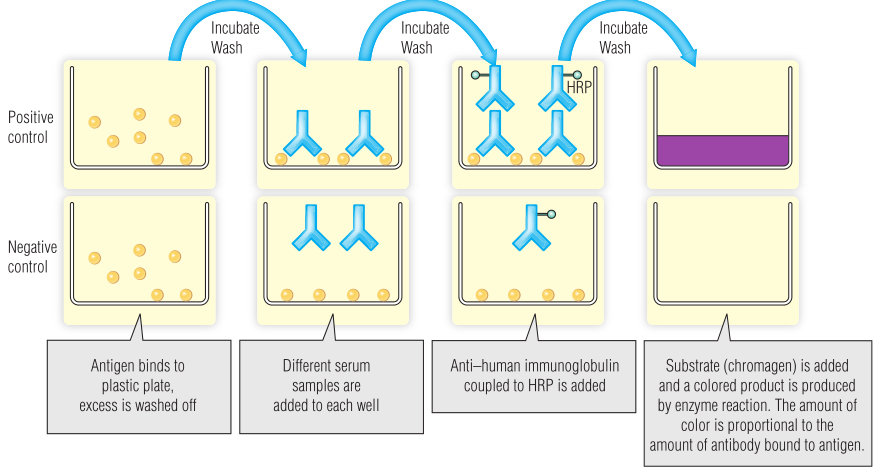

酶联免疫吸附试验

酶联免疫吸附试验(ELISA)是一种非常敏感和简单的检测,它使用与抗体相连的酶的共价复合物直接检测抗原或与抗体-抗原复合物结合(Fig 5.3)。这项实验使用的是塑料板,将相关抗原绑定在“孔”的内部。患者血清在这些孔中孵育,任何相关抗体随后都会与抗原结合。对含有无关抗体的血清进行清洗,但由于其高亲和力,与抗原结合的抗体不会受到干扰。最后,加入从动物中提取的能与酶结合的第二种抗体,将其与患者抗体结合。这种抗人免疫球蛋白将与孔中仍然存在的抗体结合。所选的酶能够催化反应,从无色底物(如碱性磷酸酶或辣根过氧化物酶[HRP];见Fig 5.3)生成有色产物。然后,与抗原结合的抗体的量与可以看到的有色最终产物的量成正比。BOX 5.2显示了如何使用ELISA来筛查传染病。

Fig 5.3 酶联免疫吸附试验(ELISA)